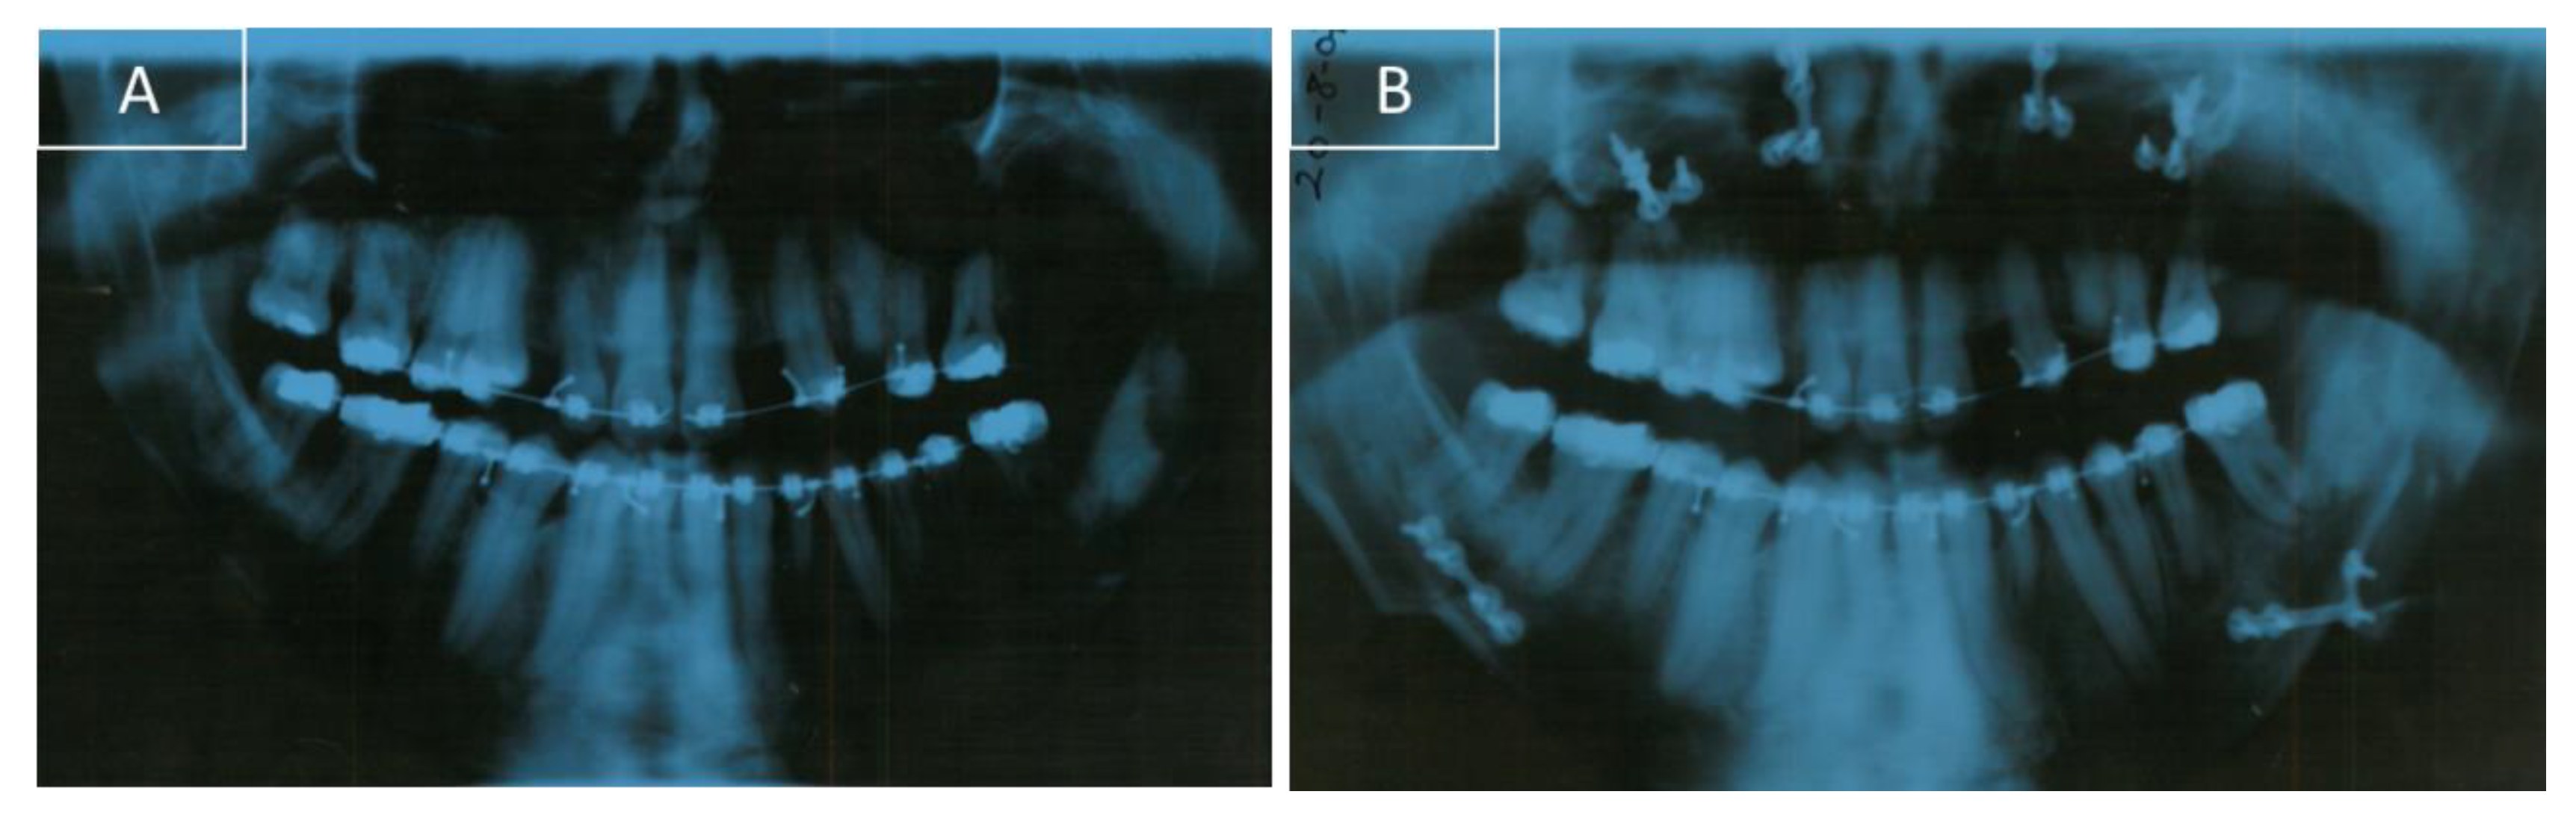

A lateral cephalogram performed before orthodontic treatment to analyze linear and angular measurements showed significant craniofacial dysmorphia (Figure 4A).

After a control orthopantomography, a radiolucency and asymptomatic lesion appeared in the left mandibular branch. To guide the surgeon in proper patient management, a computer tomography was done. The lesion was not related to the mandibular molar tooth and was surgically removed in the hospital. After three months, the patient was subjected to a LeFort I surgery to make a 5 mm superior reposition of the maxilla to reduce the gummy smile. At the same time, a bilateral sagittal split osteotomy (BSSO) was made for mandibular setback and reposition. A genioplasty for vertical reduction with 6 mm was also performed. After osteotomy, small bone plates with bone screws were used to stabilize the segments and to obtain a rigid fixation (Figure 4B and Figure 6B).

Figure 4. Cephalogram. (A) Pre-surgery and (B) post-surgery.